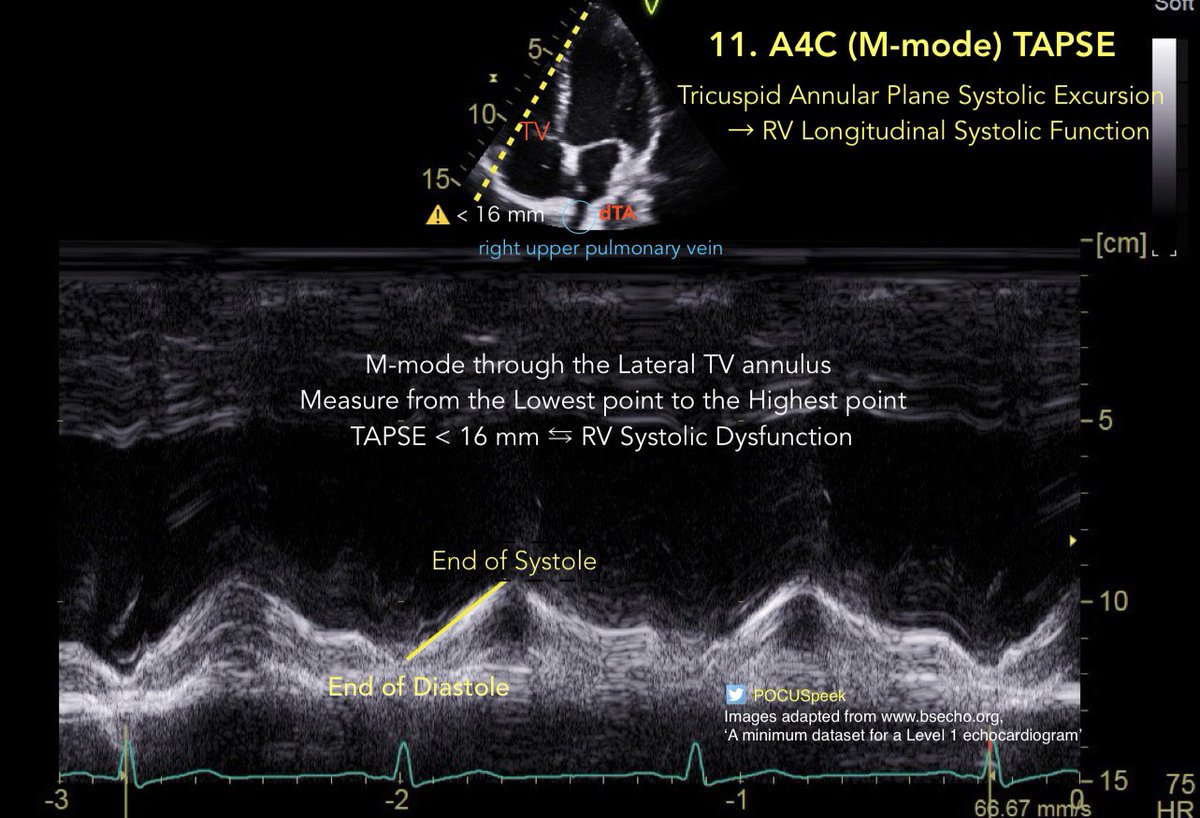

Some annotated #firstecho #POCUS main views 👇🏻 3/3

Some annotated #firstecho #POCUS main views 👇🏻1/3

Some annotated #firstecho #POCUS main views 👇🏻 2/3